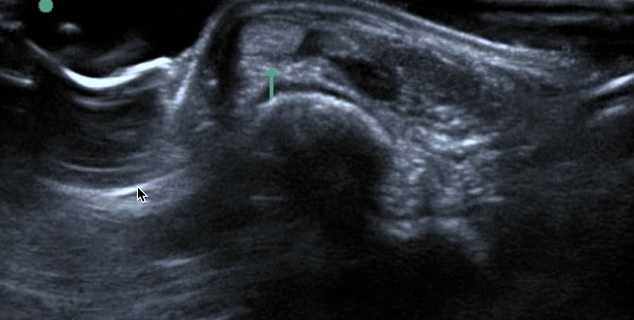

Foot & Ankle Peroneal Tendon Subluxation Image